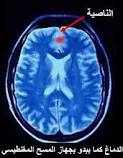

ئیعجازى زانستى لهسهر شوینى درۆکردن ( الناصیه ) له قورئاندا

ئامادهکردنى / نهجات رواندزى